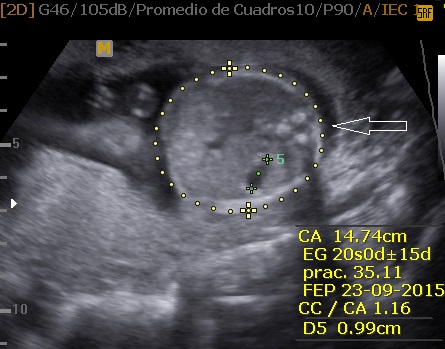

La Neurosonografía Fetal se refiere a la evaluación del Sistema Nervioso Central por Ultrasonidos: cráneo y su contenido (cerebro, ventrículos, tallo, cerebelo, etc.) y de la columna vertebral y su contenido (vértebras, médula espinal, líquido cefalorraquídeo, etc.).

Las estructuras intracraneales después de la semana 18-20 del embarazo son muy características y permanecen visualmente invariables hasta el final del embarazo, solo modificando sus tamaños a medida que el feto crece. Esto es de gran ayuda ya que permite determinar la aparición de cambios que podrían sugerir desviación de la normalidad y aparición de una malformación congénita o lesión adquirida por eventos externos especialmente relacionados a infecciones y accidentes vasculares fetales.